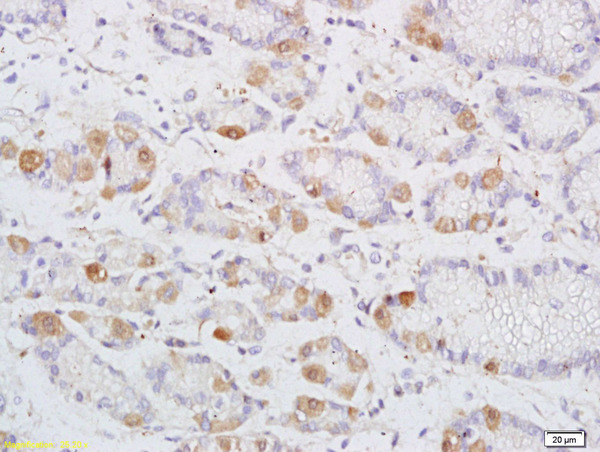

IHC-P analysis of human colon carcinoma tissue using GTX52212 DENND2D antibody.

Dilution : 1:200